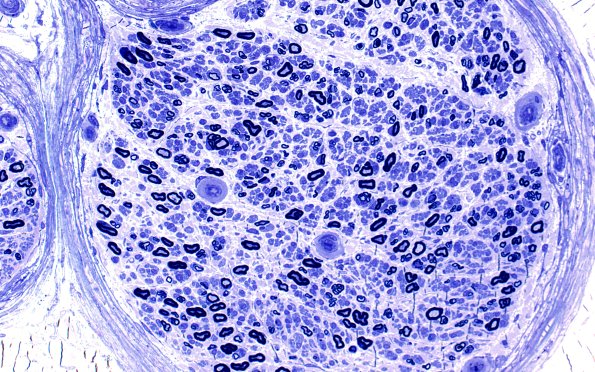

15A2 (Case 15) HIEM Plastic 20X